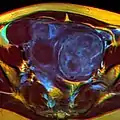

A very large (9 cm) fibroid of the uterus which is causing pelvic congestion syndrome as seen on CT

A very large (9 cm) fibroid of the uterus which is causing pelvic congestion syndrome as seen on CT A very large (9 cm) fibroid of the uterus which is causing pelvic congestion syndrome as seen on ultrasound